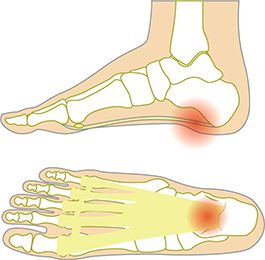

발가락 신경종 (모튼 신경종)

- 발가락 사이의 신경이 압박을 받아 염증이 생기는 질환입니다. 주로 높은 굽의 신발을 신거나 발에 무리가 가는 행동을 반복할 때 발생합니다. 통증은 발가락 사이에서 타는 듯한 느낌이나 찌릿한 통증으로 나타나며, 종종 발바닥 쪽으로도 방사됩니다.